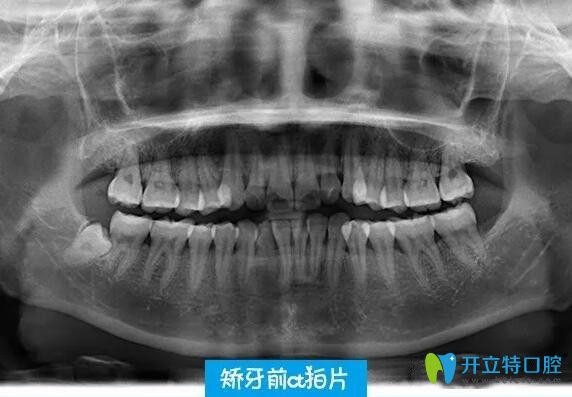

通過牙片,醫(yī)生說我的牙齒只是輕微咬合不正、有些齙牙,這種情況不用拔牙~~~確定了矯正方案,在半個月后才戴的隱適美隱形牙套~~~